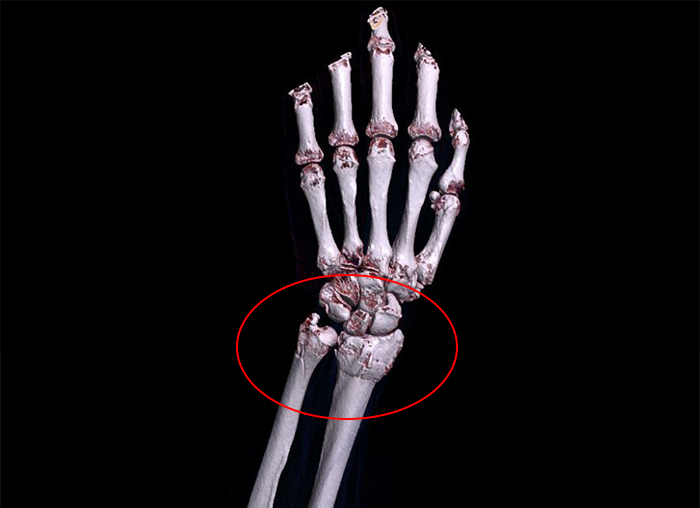

진단명:

Fx. distal radius and ulna wrist Lt.

좌측 요척골 원위부 골절

진단명은 좌측 요척골 원위부(손목 부위) 골절이었는데요. 영상 사진을 보시면 손목 뼈 부위에 금이 가 있는 것을 확인하실 수 있습니다. 손목 뼈는 수시로 움직이는 중요한 관절에 연결되어 있습니다. 그래서 조금만 잘못 붙더라도 지속적인 통증이나 관절염 증상이 나타날 수 있습니다.

그러므로 세밀하고 안정적인 골유합이 필수적인데요. 관혈적 정복술을 시행하여 금속판과 못을 삽입하여 골절된 뼈를 단단하게 고정하는 수술을 시행하였습니다.